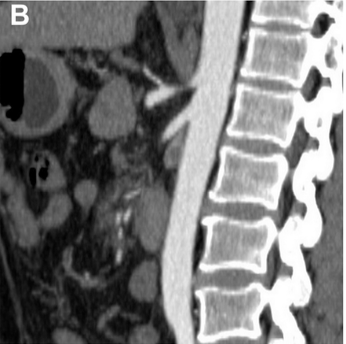

Better visualization, smarter planning. In this JVS-VL pilot study, CEUS + UHFUS showed promise for improving preop mapping and streamlining LVA in patients with lymphedema.